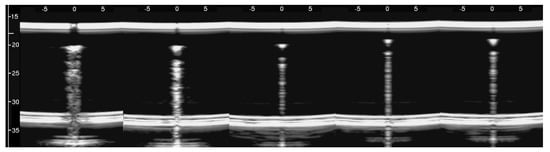

Figure 2. Two ultrasound vertical artifacts with different zoom degrees, which were obtained on the models illustrated in the left image of Figure 1, are shown. The pair of short artifacts a1 is provided by multiple reflections between the two air cylinders which limit the aperture of the trap. The longer artifact a2 is generated by the re-radiation of the acoustic energy and starts when the beam is reflected from the bottom of the trap.

The above tests on the PVC box provided important indications. First of all, the confirmation that the artifacts observed on the ultrasound pulmonary images are probably generated by multiple reflections between the aerated spaces, since the images acquired on the box in the presence of a single air cylinder did not show any artifacts. Moreover, tests on simulated single traps did not give rise to artifacts of significant length. Only in the case of the artifact in Figure 2, which was generated by the seven air cylinders, was an artifact of 12 cm observed. Besides the length of the artifacts, however, another problem arose from the previous tests: none of the artifacts obtained with the air cylinders in agar gel showed those clearly modulated artifacts which are often observed in cardiogenic patients.